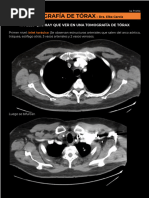

Ya en un corte tomográfico con mayor amplitud, se observan los lobulillos pulmonares.

Cada lobulillo está limitado por la pared/borde o septos interlobulillares. Todos los

lobulillos van a tener una arteriola central, en el caso de la imagen, es el punto blanco

que se observa dentro del lobulillo (forma hexagonal). La definición del corte

tomográfico no permite ver el bronquiolo, pero DEBE estar ahí acompañando a la

arteriola. Recordar que recorriendo a los septos interlobulillares habrá vénulas y

linfáticos.

Hay lobulillos a nivel del pulmón central y pulmón periférico. Estos lobulillos se ven

bien delimitados (en la imagen) porque YA hay patología, en un paciente sano no.